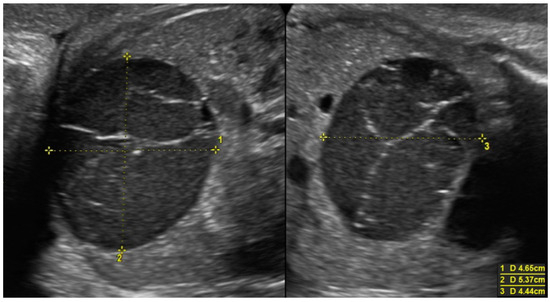

Figure 3. Voluminous ovarian cyst with hemorrhagic content in a female fetus at 35 weeks of pregnancy (46 × 54 × 44 mm). At 37 weeks of pregnancy, the formation regressed spontaneously, and at the ultrasound after delivery, multifollicular ovaries were described.